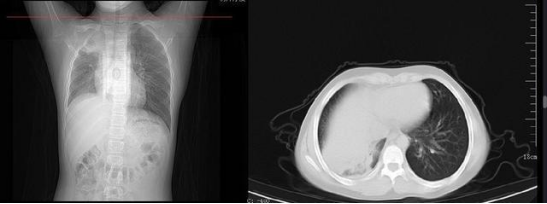

新冠病毒感染導致肺纖維化高發(fā)

肺部作為新冠病毒主要攻擊的器官之一,往往是后遺癥的“重災區(qū)”, 嚴重炎癥風景導致肺部出現(xiàn)炎性組織損傷,會出現(xiàn)結(jié)構(gòu)破壞,“瘢痕組織”生長,導致肺組織變硬,彈性差、氣體通過困難包,導致了患者長期的呼吸困難。

在 2020 年新冠疫情剛開始時,病毒會對肺部造成明顯影響,肺部 CT 變化也是確診的重要標志。而如今奧密克戎時代,大約還是有 10% 的感染者會發(fā)展為普通型或重癥,表現(xiàn)出輕重不一的肺炎表現(xiàn)。

這幾天,網(wǎng)上關于感染奧密克戎后出現(xiàn)“白肺”的消息越來越多。

武漢一 12 歲男孩感染新冠后,家長擔心去醫(yī)院會交叉感染,于是在家硬扛,咳嗽一周不就醫(yī),后來家長發(fā)現(xiàn)癥狀沒有好轉(zhuǎn),甚至開始嘔吐,這才將他送醫(yī)院就診,醫(yī)生一查已發(fā)展成肺炎,一側(cè)肺部已經(jīng)成了“白肺”。盡管經(jīng)過治療,男孩的癥狀已經(jīng)好轉(zhuǎn),但也留下了后遺癥——肺部纖維化。

同濟大學附屬上海市肺科醫(yī)院呼吸監(jiān)護室副主任醫(yī)師張黎就“白肺”問題進行解讀:“重癥的白肺患者,死亡率在 40% 以上,還是有一部分人是可以治愈的。但是要想讓肺恢復到本來干干凈凈的狀態(tài),是比較難的,絕大部分患者會留下肺部纖維化的后遺癥。之前有專家統(tǒng)計過,在感染新冠德爾塔毒株并康復一年后,患者的肺功能會恢復,但是恢復態(tài)勢不會保持太久就會呈下降趨勢,且這種下降是不可逆的。”

《Nature Medicine 》2021 年發(fā)表了:Post-acute COVID-19 syndrome,研究指出呼吸困難在 60~100 天的隨訪期內(nèi)的發(fā)生率為 42%~66%,有 6.6% 的患者因持續(xù)低氧血癥需要補充氧氣。患者出院后 3 個月評估發(fā)現(xiàn)約 25% 的輕度至中度病例存在纖維化,在重癥病例居多的隊列中,約 65% 的康復者存在肺纖維化。